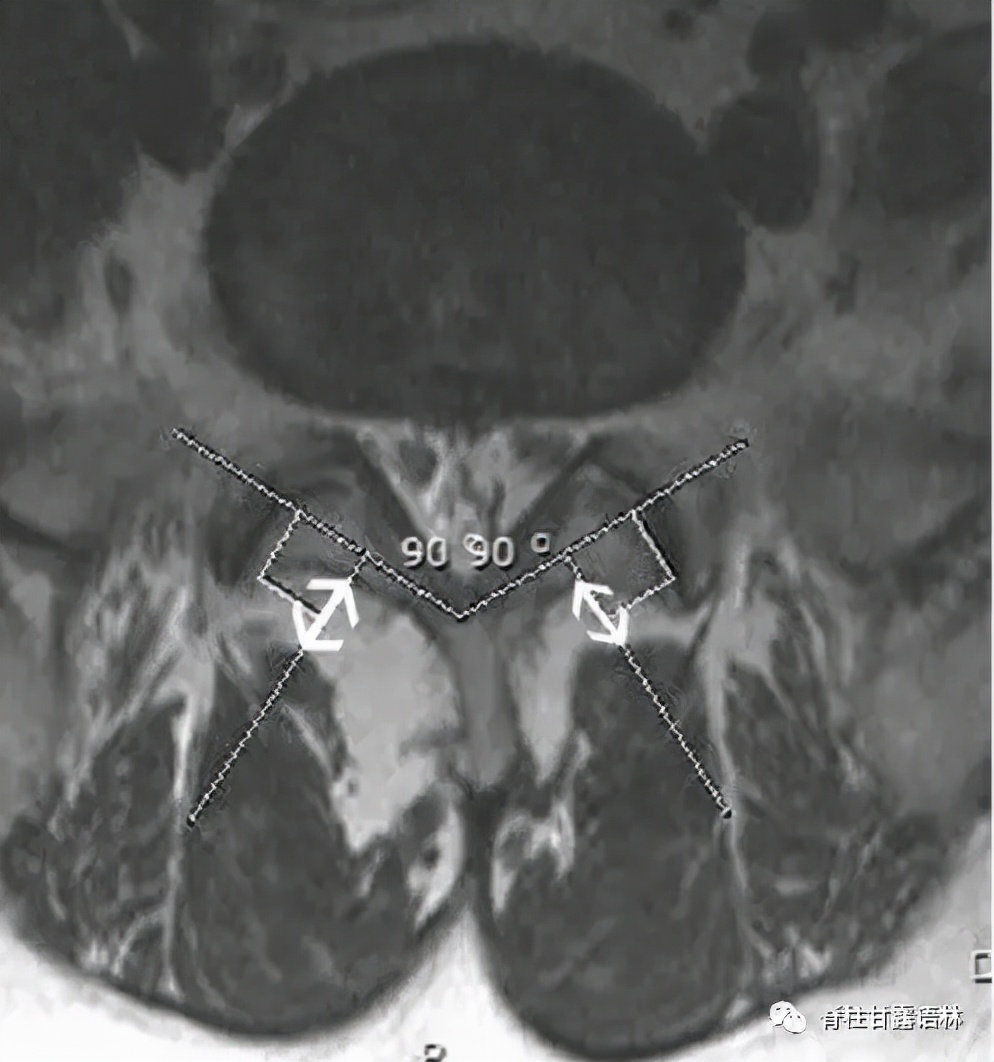

- 学界以MRI研究腰突与多裂肌,常以横截面积CSA(图5),评估两侧对称与否;亦有以多裂肌至椎板之垂直距离MLD加以研究者(图6)。

图5 腰4/5椎间盘平面多裂肌与腰大肌横截面积之测定